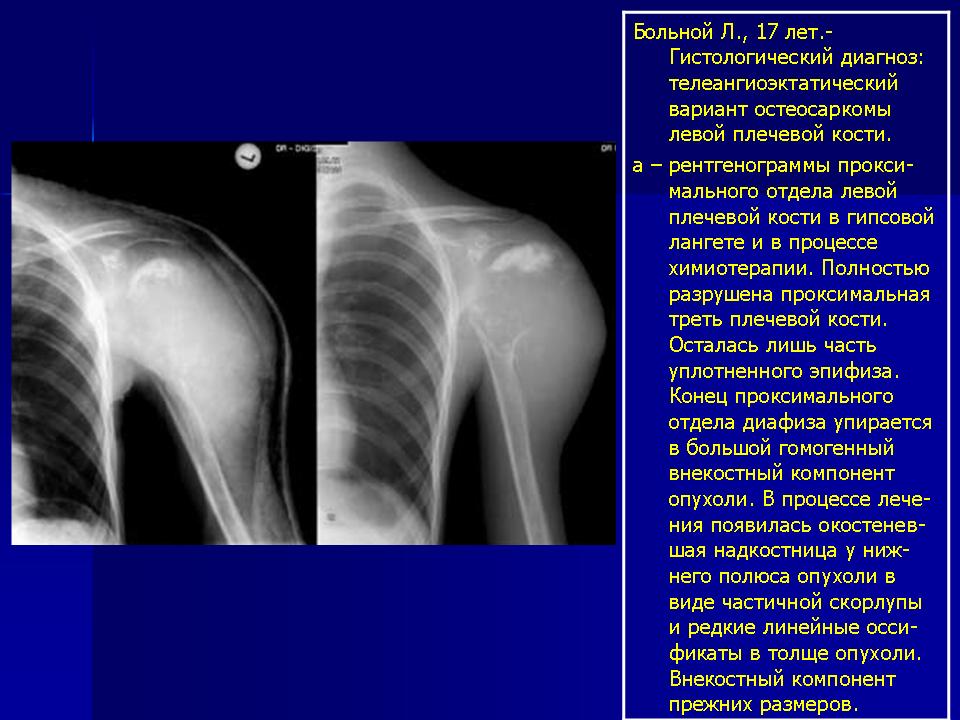

Остеогенная саркома — очень злокачественная опухоль. По частоте возникновения занимает первое место, составляя, по данным D.C.Dahlin (1967), наблюдавшего 650 больных с остеогенной саркомой, 39 % всех больных с саркомами. Из 650 больных с остеогенной саркомой у 20 она возникла в костях, пораженных болезнью Педжета, у 2 — фибросаркомой и у 1 больного — гигантоклеточной опухолью. Чаще она встречалась у лиц мужского пола (62 %). По данным ВОНЦ АМН РФ, с 1952 по 1985 г. лечилось 350 больных с остеогенной саркомой, что составило 38,3 % больных с саркомой костей. В 1922 г. J.Ewing предложил называть саркомы, происходящие из костных клеток, «остеогенными саркомами», следовательно, в эту группу опухолей входили и паростальная саркома, и хондросаркома. Последующими исследователями был внесен целый ряд уточнений [Виноградова Т.П., 1973; Kolodny А., 1927; Phemister D.W., 1930; Geschickter C.F., Copeland M.M., 1951], в результате чего пришли к единому мнению, выраженному в международной гистологической классификации костных опухолей 1974 г.: остеосаркома, остеогенная саркома — это злокачественная опухоль, характеризующаяся непосредственным образованием кости или остеоида опухолевыми клетками. Обнаружение в клетках опухоли щелочной фосфатазы с помощью гистохимического исследования может помочь проведению дифференциальной диагностики. Т.П.Виноградова (1973) особенно подчеркивала, что хотя и принят термин «остеогенная саркома» (происходящая из костеобразующей ткани), ее правильнее было бы называть «остеогенетической саркомой», т.е. образующей костную ткань; следовательно, правомочен также термин «остеопластическая» независимо от того, имеется ли остеопоротическая или остеосклеротическая форма. Т.П.Виноградова принципиально возражала и против употребления широко распространенного названия «остеосаркома», считая его собирательным, неточным. Остеогенная саркома, как правило, возникает в одной кости, но описаны и множественные поражения костей, а также возникновение остеогенной саркомы у 2 сестер и брата практически в одно и то же время [Roberts C.W., Roberts С.P., 1935]. Предположение, что остеогенная саркома возникает из мультипотентных мезенхимальных клеток, подтверждается, по нашему мнению, тем фактом, что описаны больные с внескелетными остеогенными саркомами, развивающимися в мыщцах, матке, почках, щитовидной железе, молочной железе и других тканях, причем опухоли не связаны с рядом расположенными костями. О внескелетных остеогенных саркомах упоминает и Т.П.Виноградова (1973). R.Lorentzon и соавт. (1979) сообщили о 4 больных, из которых в течение 2 лет умерли трое и один жив 14 лет. По данным этих авторов, в 1978 г. в англоязычной литературе описано 107 больных с внекостной остеогенной саркомой, средний возраст которых составил 51 год. Рецидивы опухоли возникают как правило, поэтому необходимы широкие резекции с соблюдением принципа зональности и футлярности, а также современная полихимиотерапия. R.I.Ferguson, E.I.Junis (1978) на основании электронно-микроскопического изучения остеогенных сарком идентифицирует следующие типы клеток: примитивные недифференцированные мезенхимальные клетки и клетки с морфологическими признаками остеобластов, хондробластов и фибробластов в сочетании с многоядерными клетками, часть из которых подобны остеокластам, тогда как в других клетках имеются анапластические и дегенеративные изменения. Авторы полагают, что эти примитивные мезенхимальные клетки являются плюрипотенциальными клетками, способными дифференцироваться в различные клетки. К подобным выводам пришли Л.В.Литвинова (1976), D.Katenkamp и др. (1978), E.Grundmako и соавт. (1981). A.Roessner и соавт. к указанным видам клеток прибавили клетки ангиогенной природы и миофибробластической дифференцировки. В.Ф.Кондаленко и др. (1987) при электронно-микроскопическом исследовании остеогенных и паростальных сарком обнаружили различия во внеклеточном матриксе, в частности протеогликанов. Они считают, что отличие в структуре протеогликанов обусловливает направление и уровень дифференцировки клеток опухоли, что и определяет степень злокачественности опухоли. Так, они обнаружили резкое отличие в структуре протеогликанов в матриксе паростальной и остеогенной сарком, которые клинически резко различаются в своей злокачественности. Электронно-микроскопические данные свидетельствуют о том, что остеогенная саркома, как и другие виды опухолей, может происходить из примитивных недифференцированных мезенхимальных клеток, прямо связанных с рядом биохимических процессов; некоторые из них приведены ниже. В опухолевых клетках тканеспецифические белки отсутствуют или их очень мало, как и ферментов, характерных для нормальных тканей. На этом основании считают, что предшественниками опухолевых клеток являются низкодифференцированные клетки [Potter V.R., 1969, и др.] или возникновение злокачественных опухолей (клеток) связано с процессом недифференцировки, или ретродифференцировки, — процессом, который предшествует появлению опухолевых клеток [Оленев Ю.М., 1977; Uriel J., 1979; Curtin N.J., Snell К., 1983]. Прямое участие в развитии опухолевых клеток принимают ферменты, которые подразделяют на две группы: 1) ферменты, обеспечивающие процесс пролиферации, и 2) ферменты, включенные в системы передачи в клетку регуляторных сигналов извне, т.е. осуществляющие регуляцию пролиферации [Ходостова И.А., 1988]. Длительное время как о чем-то таинственном говорилось об автономности опухолевого роста. Эта особенность присуща опухолевым клеткам и определяет их свойства, но необъяснима. В последние годы было показано, что некоторые протеинкиназы находятся в связи с рецепторами факторов роста, а системы циклических нуклеотидов и ферментов их метаболизма приобретают важное значение в делении клеток нормальных тканей. Было обнаружено также, и это особенно важно, что в опухолевых тканях имеются существенные отклонения характеристик ряда ферментов, участвующих в пролиферации клеток. Это и определяет их автономный рост. Так объясняется с биохимических позиций автономность роста опухоли. И наконец, клетка обладает, с одной стороны, возможностью активировать положительные, необходимые в данное время процессы, а с другой — давать начало процессам, отрицательно отражающимся на функции всего организма или какого-либо органа, ткани. Процессы регуляции активности генов деятельности ДНК (торможение ее функции) происходят в результате сложных процессов, одним из которых является метилирование ДНК ферментами ДНК — метилазами. Химические канцерогены нарушают, изменяют, снижают процесс метилирования ДНК, в результате чего ряд генов (онкогены), кодирующих синтез белков и определяющих появление опухолевых клеток, начинают функционировать и вызывают дифференцировку примитивных недифференцированных мезенхимальных клеток в опухолевую ткань. Нужно помнить, что гены состоят из четырех нуклеотидных оснований: аденина (А), темина (Т), цитозина (Ц), гуанина (Г). Разные комбинации А, Т, Ц и Г кодируют различные белки. Как известно, в 1960 г. была открыта согласуемая хромосомная аберрация в опухолевых клетках при хронической миеломной лейкемии, и с тех пор продолжаются исследования хромосом с точки зрения ракового цитогенеза. N.Mandahl и A.Rydholm (1989) опубликовали данные, полученные ими и другими исследователями, изучавшими изменения в хромосомах у больных со следующими опухолями костей: саркомой Юинга, остеогенной саркомой, хондромами, хондросаркомами, злокачественной фиброзной гистиоцитомой, синовиальной саркомой, липомой, липосаркомой и некоторыми другими. При остеогенной саркоме только в незначительном числе клеток хромосомы оставались неизменными, а в большинстве клеток были обнаружены сложные изменения в наборах хромосом, наблюдались клетки как гиподиплоидные, так и приближающиеся почти до гексадиплоидного уровня, в большинстве опухолей обнаруживались участки с триплоидными и тетраплоидными клетками. Можно надеяться, что изучение хромосом злокачественных опухолей позволит лучше понять процессы, происходящие в клетках. Н.А.Краевский и Ю.Н.Соловьев (1971) описали важные наблюдения, имеющие значение в патои морфогенезе остеогенной саркомы. В теоретическом аспекте они исходили из известного положения о предшествующих опухолевому росту явлениях диспластического и дистрофического характера, согласно которому глубокие метаболические нарушения, приводящие к изменениям в клетках и тканях, влияют на их дифференцировку и являются обязательным условием возникновения опухолей. Изменения энхондрального остеогенеза непосредственно связаны с процессами кровоснабжения и особенностями метаболизма хрящевой ткани зоны роста длинных трубчатых костей, что приводит к нарушению процессов превращения хрящевой ткани в костную, а в период интенсивного роста кости может обусловить появление диспластической хрящевой ткани. Изучение костей, пораженных остеогенной саркомой, у ряда больных в возрасте 12—18 лет позволило Н.А.Краевскому и Ю.Н.Соловьеву выявить отчетливые признаки задержки резорбции хряща и смещение участков метафизарной спонгиозы по оси в диафизарном направлении с отрывом их от эпифизарной хрящевой пластинки. Фактически подобные изменения представляют собой полный аналог зоны, или «пояска» (в известной мере эктопированного), костеобразования, которое наблюдается и при экспериментальном воспроизведении опухолей скелета. Единственным реальным объяснением этого явления может быть только трактовка его с позиции нарушения синхронности процессов костеобразования (энхондрального остеогенеза) и процесса роста кости. Как показали исследования Ederer (1965) и J.E.Fraumani (1967), существует достоверный параллелизм между увеличением и ускорением роста в возрасте 12—17 лет и частотой возникновения остеогенной саркомы. По данным Ю.Н.Соловьева (1959), редукция сосудистого русла костей вблизи зон роста у экспериментальных животных приводит к угнетению энхондрального остеогенеза в зонах роста и персистенции хряща эпифизарных пластинок. По сообщению Н.А.Краевского и Ю.Н.Соловьева, у 98,5 % больных остеогенная саркома возникла в длинных трубчатых костях, а у 80 % развилась в дистальном конце бедренной кости и проксимальных концах большеберцовой и малоберцовой костей, т.е. ростковых зонах, обладающих наибольшей скоростью роста. Известно, что остеогенная саркома наблюдается у пород собак высокого роста и не встречается у низкорослых собак, что нужно прямо связать со скоростью роста костей за счет эпифизарных зон. В настоящее время морфологические данные являются основой, на которой строятся наши представления о патогенезе и развитии опухолей. Процессы, определяющие опухолевые клетки и предшествующие возникновению опухоли как таковой, известны, но не настолько детально изучены, чтобы в своей практической деятельности врачи различных специальностей могли бы улавливать момент возникновения опухоли, точную ее локализацию и направленность изменений биохимических процессов в межклеточной субстанции, которые определяют возникновение новой опухолевой популяции клеток, развивающихся из мезенхимальных клеток — клеток-предшественников, стволовых клеток. Следует считать, что опухолевые клетки возникают под влиянием воздействия многочисленных физических (малоизученных), биохимических нарушений, а также атомных, молекулярных метаболических отклонений, которые приводят к изменениям генов и нарушениям в ДНК, обусловливающим начало опухолевого роста. Н.Н.Трапезников и соавт. (1983) указывали, что во втором десятилетии жизни возникают 80 % остеогенных сарком, при этом у мальчиков 11 — 15 лет они встречаются реже (37,5 %), чем у девочек того же возраста (62,5 %). Противоположное соотношение наблюдается в следующее пятилетие: среди мужчин 16—20 лет опухоль развивается у 62,5 %, а среди женщин того же возраста — у 37,5 %. Приведенные статистические данные с несомненностью говорят о значении эндокринных влияний, скорости роста длинных трубчатых костей в длину за счет зон роста костей, где возникает 97 % опухолей, а в 80 % опухолей развиваются в зонах с наиболее интенсивным ростом: это нижний метафиз бедренной кости, верхний метафиз плечевой кости, затем следуют кости таза, верхняя и нижняя челюсти, позвоночник, ребра, лопатка, кости предплечья, стопы, кисти, при этом определенную роль играет размер площади зоны роста. Отмечено, что у подростков, юношей, девушек высокого роста вероятность возникновения опухоли больше. Некоторые авторы считают, что травма может способствовать началу развития опухоли, если имеется «готовность» тканей к опухолевому процессу, а по мнению других — если имеются бластоматозные клетки. Согласно нашим наблюдениям травма способствовала лишь выявлению уже существовавшего опухолевого процесса. Клиническая картина остеогенной саркомы характерна и соответствует проявлениям быстро растущих злокачественных опухолей. Особенно характерна боль, появляющаяся раньше видимой опухоли; сильная боль отмечается днем и ночью, рано развиваются атрофия мышц, сгибательная контрактура в суставе (наиболее часто в коленном). Повышение местной температуры, истощение, усиленная сеть подкожных вен, метастазы в легких появляются позднее. У части больных все клинические проявления протекают бурно, а у другой части — они менее выражены и развитие опухоли происходит медленнее. Рентгенологическая картина зависит от многих причин: центрального или периферического расположения очага опухоли, превалирования тех или иных гистологических структур, процессов, сопровождающих рост опухоли. Принято выделять остеолитический и остеосклеротический варианты, а также хондробластический и телеангиэктатический типы остеогенной саркомы. Согласно данным Н.Н.Трапезникова, Л.А.Ереминой, Ю.Н.Соловьева и др. менее агрессивное течение наблюдается при остеосклеротическом и хондробластическом типах и более агрессивное — при остеолитическом и телеангиэктатическом типах, однако это бывает не всегда, так как при остеосклеротическом типе возможно и очень злокачественное течение. При остеолитическом типе наблюдаются преимущественно процессы разрушения, лизиса кости; при телеангиэктатическом типе наряду с разрушениями происходит формирование плотных костных опухолевых масс, имеющих на рентгенограммах характерный склеротический вид. Широко известны такие рентгенологические симптомы, как спикулы и периостальный козырек Кодмана. У некоторых больных эти симптомы нерезко выражены, и тогда диагностика представляет значительные трудности; ошибки в диагнозе ведут к неправильному лечению. Сцинтиграфия является ценным диагностическим методом, позволяющим рано выявить первичный очаг и определить состояние всего скелета. Е.К.Колесникова и А.В.Забродина (1988) показали, что возможности компьютерной томографии в диагностике остеогенной саркомы очень велики, поскольку хорошо видны такие изменения кортикального слоя кости, как разрыхление, расслоение, прерывистость, а также изменения надкостницы, ее отслоение, появление спикул, хорошо виден внекостный компонент опухоли. Гистологическое строение остеогенной саркомы весьма разнообразно. Это относится как к разным больным, так и к различным участкам опухоли. Клетки то напоминают остеобласты, то имеют округленную, веретенообразную форму. В опухолевой ткани характерно наличие большего или меньшего количества атипичных костных обызвествленных или необызвествленных остеоидных структур (Т.П.Виноградова). Тщательно проведенные на большом материале исследования И.В.Забродиной (1995) показали, что в 9,8 % случаев метастазы остеогенной саркомы выявляются в костях при еще интактных легких. Это еще раз подтверждает нашу гипотезу, что метастазирование возникает более легко и, следовательно, чаще в тканях, которые по строению близки к ткани опухоли, когда сходно строение «географических мембран» клеток опухолей и клеток тканей. И.В.Забродиной (1995) детально разработаны критерии ранней диагностики опухоли в зависимости от ее локализации: губчатая кость, кортикальная кость, периост. Она также описала две редкие локализации остеогенной саркомы — интракортикальную и периостальную. Для остеогенных сарком характерно метастазирование в легкие (95 %), сравнительно редко в другие кости (около 10 %), мышцу сердца и т.п. обычно в финальной стадии (гематогенный путь метастазирования), что резко ухудшает прогноз. В недалеком прошлом все авторы указывали на плохие результаты лечения (хирургического, лучевого, химиотерапевтического) у большинства больных. С.А.Райнберг (1964) писал: «Прогноз при остеогенной саркоме чрезвычайно неблагоприятен. Болезнь всегда ведет к смерти..., обычные случаи «излечения» остеогенных сарком при помощи того или иного способа лечения — хирургического, лучевого или химиотерапии — относятся к диагностическим ошибкам». Динамическое наблюдение за больными с остеогенной саркомой позволило R.Marcow и соавт. (1970), N.Jaffe и соавт. (1974), E.Cortes и соавт. (1974), C.Pratt и соавт. (1974), Z.Matejovsky и соавт. (1975), Н.Н.Трапезникову, Л.А.Ереминой и др. считать, что клинически не определяемые метастазы в легких и других органах существовали ко времени диагностирования поражения кости и что остеогенную саркому условно можно расценивать как «системное» заболевание. Следовательно, необходимо одновременное лечебное воздействие как на очаг в кости, так и на метастазы в легких, иначе больной погибнет. Особенно трудно лечить больного с метастазами в легкие, поскольку биологические свойства метастазов изменяются. П.А.Боговский писал: «При всех этих разновидностях рецидива в гистологических препаратах можно обнаружить такую же морфологическую структуру, как и в первичном очаге. В таких случаях, исходя из положения о несопряженной прогрессии свойств опухоли, можно допустить, что возникла новая популяция опухолевых клеток, у которых прогрессировали не морфологические признаки, а, напротив, способность метастазировать или (после лечения) резистентность к лекарственным препаратам или облучению» (выделено мною. — С.З.). А.Н.Феденко и П.А.Синюков (1989) писали, что первичная остеогенная саркома и ее метастазы в легких близки по своему строению. Все эти явления хорошо известны врачам, к сожалению, положительные результаты химиоили лучевой терапии сменяются у части больных быстрым ростом злокачественной опухоли. В отделении костной патологии взрослых ЦИТО лечилось 111 больных с остеогенной саркомой, из них 104 были оперированы. Возраст больных: 16—20 лет — 38 больных, 21—30 лет — 41, 31—40 лет 15, 41-50 лет 8, 51-60 лет 6, 61-70 лет 2, 71-80 лет 1 больной. Локализация опухоли: бедренная кость — 58 больных, большеберцовая — 21, плечевая — 12, кости таза — 6, малоберцовая кость — 3, лучевая — 4, локтевая — 1, обе кости — 1, шейный позвонок — 1, поясничный — 1, крестец — 2 больных. Большинство из них было стационировано в 1957— 1975 гг., поскольку, не имея возможности проводить современную химиотерапию, последние 20 лет мы направляли больных в специализированные онкологические отделения. Телеангиэктатическая форма остеогенной саркомы протекает очень неблагоприятно. Мы наблюдали 12 больных с этой формой, что составляет 10,8 % всех больных с остеогенной саркомой. У нас создалось впечатление, что у больных с данной формой болевые ощущения несколько меньше. Этот вид саркомы протекает очень злокачественно, только на ранних стадиях поражение ограничивается костью, как правило, метафизарного отдела, реакция надкостницы бывает незначительной, опухоль рано выходит за пределы кости, и, кроме внекостного ограниченного мягкотканного компонента, наблюдается пастозность окружающих мягких тканей. Вот почему так трудно, а чаще невозможно определить границы этого вида остеогенной саркомы в мягких тканях и произвести сохранную операцию. С.А.Покровский (1954), описывая телеангиэктатический вариант остеогенной саркомы, высказывал мнение, что она относится к опухолям кровеносных сосудов кости и является кавернозной ангиосаркомой. Наличие различного размера сосудистых кист обусловливает и особую рентгенологическую картину, которая заставляет проводить дифференциальную диагностику с аневризматической кистой кости, гигантоклеточной опухолью, сосудистыми опухолями. A.G.Huvos, G.Rosen и др. (1982) с 1921 по 1979 г. наблюдали 124 больных с телеангиэктатической формой остеогенной саркомы, которые составили 11 % всех больных с остеогенной саркомой. Возраст больных колебался от 3 до 67 лет; мужчин было 74—60 %, женщин — 50—40 %. Как и при других формах остеогенных сарком, она наиболее часто встречалась в возрасте 11—16 лет. У 36 пациентов был патологический перелом, что объясняется выраженным лизисом кости с возникновением кистозных образований, стенки которых состояли из опухолевых клеток. С 1975 г., когда начали проводить комбинированные методы лечения (преди послеоперационная химиотерапия — высокие дозы метотрексата, адриомицин или блеомицин, циклофосфан и дактиномицин), результаты лечения стали лучше.